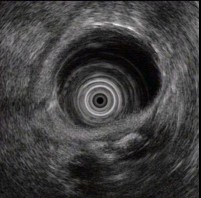

(单选题)胰腺超声内镜如图,最可能的诊断是()。

A:胆管结石

B:急性胰腺炎

C:胰腺癌

D:慢性胰腺炎

E:胰腺囊腺癌